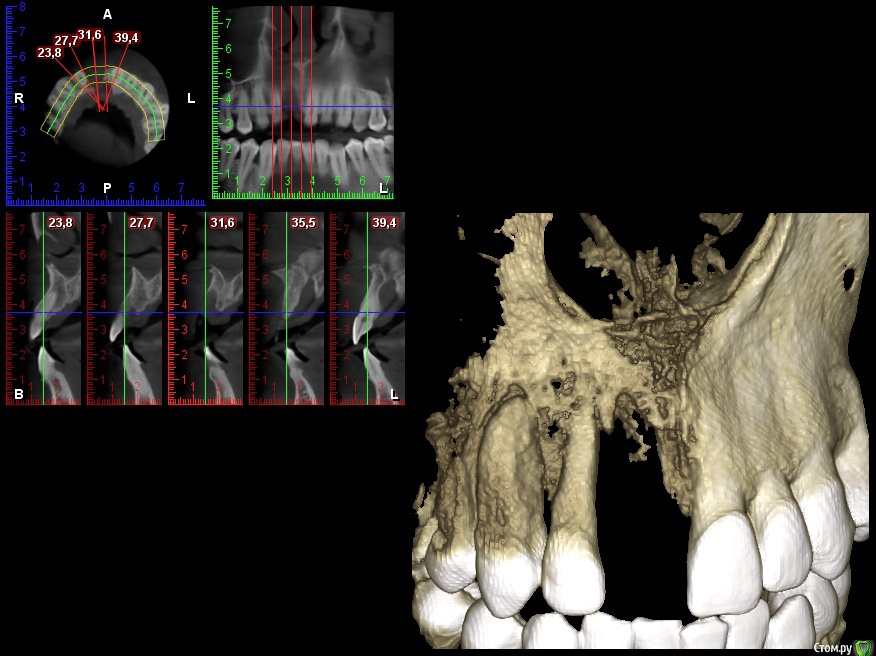

Dc.Petrov Опубликовано 4 мая, 2016 Поделиться Опубликовано 4 мая, 2016 Травма около 2 мес назад + травматичное удаление. Итог на фото.12 неподвижен. Вопрос : удастся ли с помощью нкр сделать кость для имплантации? Ссылка на комментарий

Mane Опубликовано 4 мая, 2016 Поделиться Опубликовано 4 мая, 2016 По кт медиального пика у 12 нет. Но он может быть на прицелке. Если и там нет, то 12 на выход. 5 Ссылка на комментарий

Dc.Petrov Опубликовано 5 мая, 2016 Автор Поделиться Опубликовано 5 мая, 2016 (изменено) медиального пика у 12 нет однозначно, медиальная поверхность корня визуализируется между складками десны Изменено 5 мая, 2016 пользователем Dc.Petrov Ссылка на комментарий